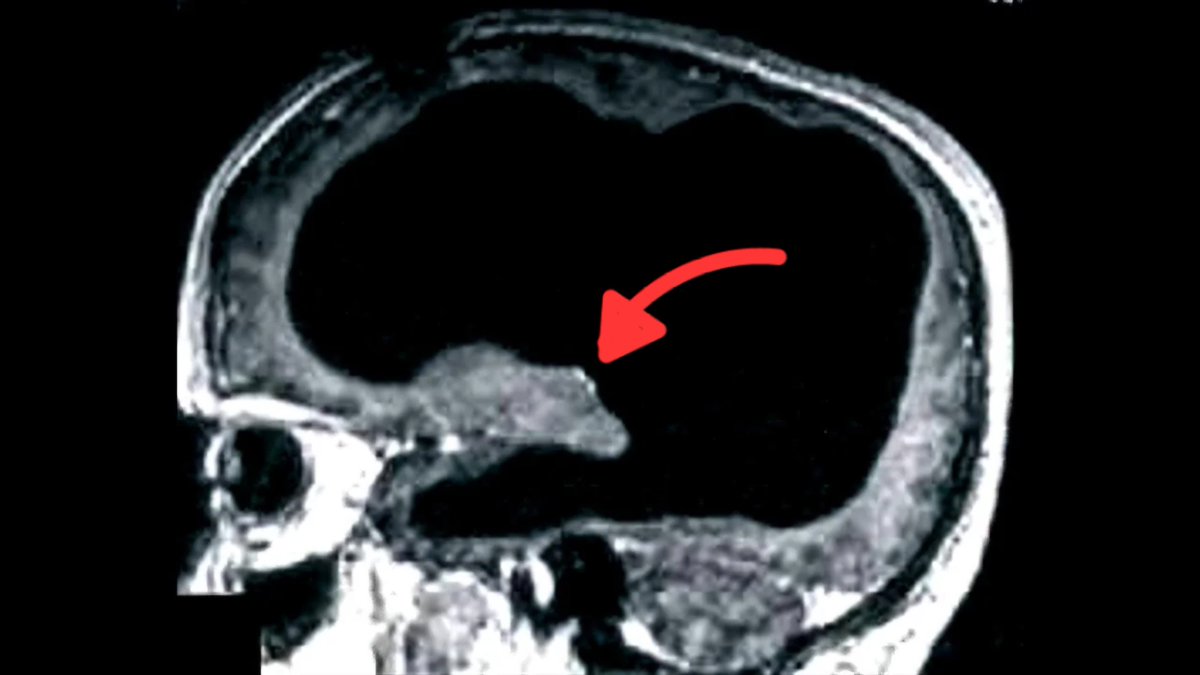

في أحد الأيام، بدأ يشتكي من ضعف بسيط في قدمه اليسرى، قرر الذهاب للطبيب، أجرى الأطباء سلسلة من الفحوصات، بما في ذلك تصوير للدماغ بالأشعة لاكتشاف سبب اعراضه، الذي ظهر في الشاشة صدم الفريق الطبي. كان امامهم فراغ كبير في رأسه.

اظهر الفحص شيئا استثنائيا: كانت جمجمته مليئة بالسائل النخاعي إلى حد كبير ولم يتبقى الا طبقة رقيقة فقط من نسيج الدماغ. تعرف هذه الحالة باسم الاستسقاء الدماغي او hydrocephalus

لكن مدى حالته غير مسبوق،كان فاقد لـ 90% من كتلة دماغه، بمعنى انه يعيش بـ 10% دماغ